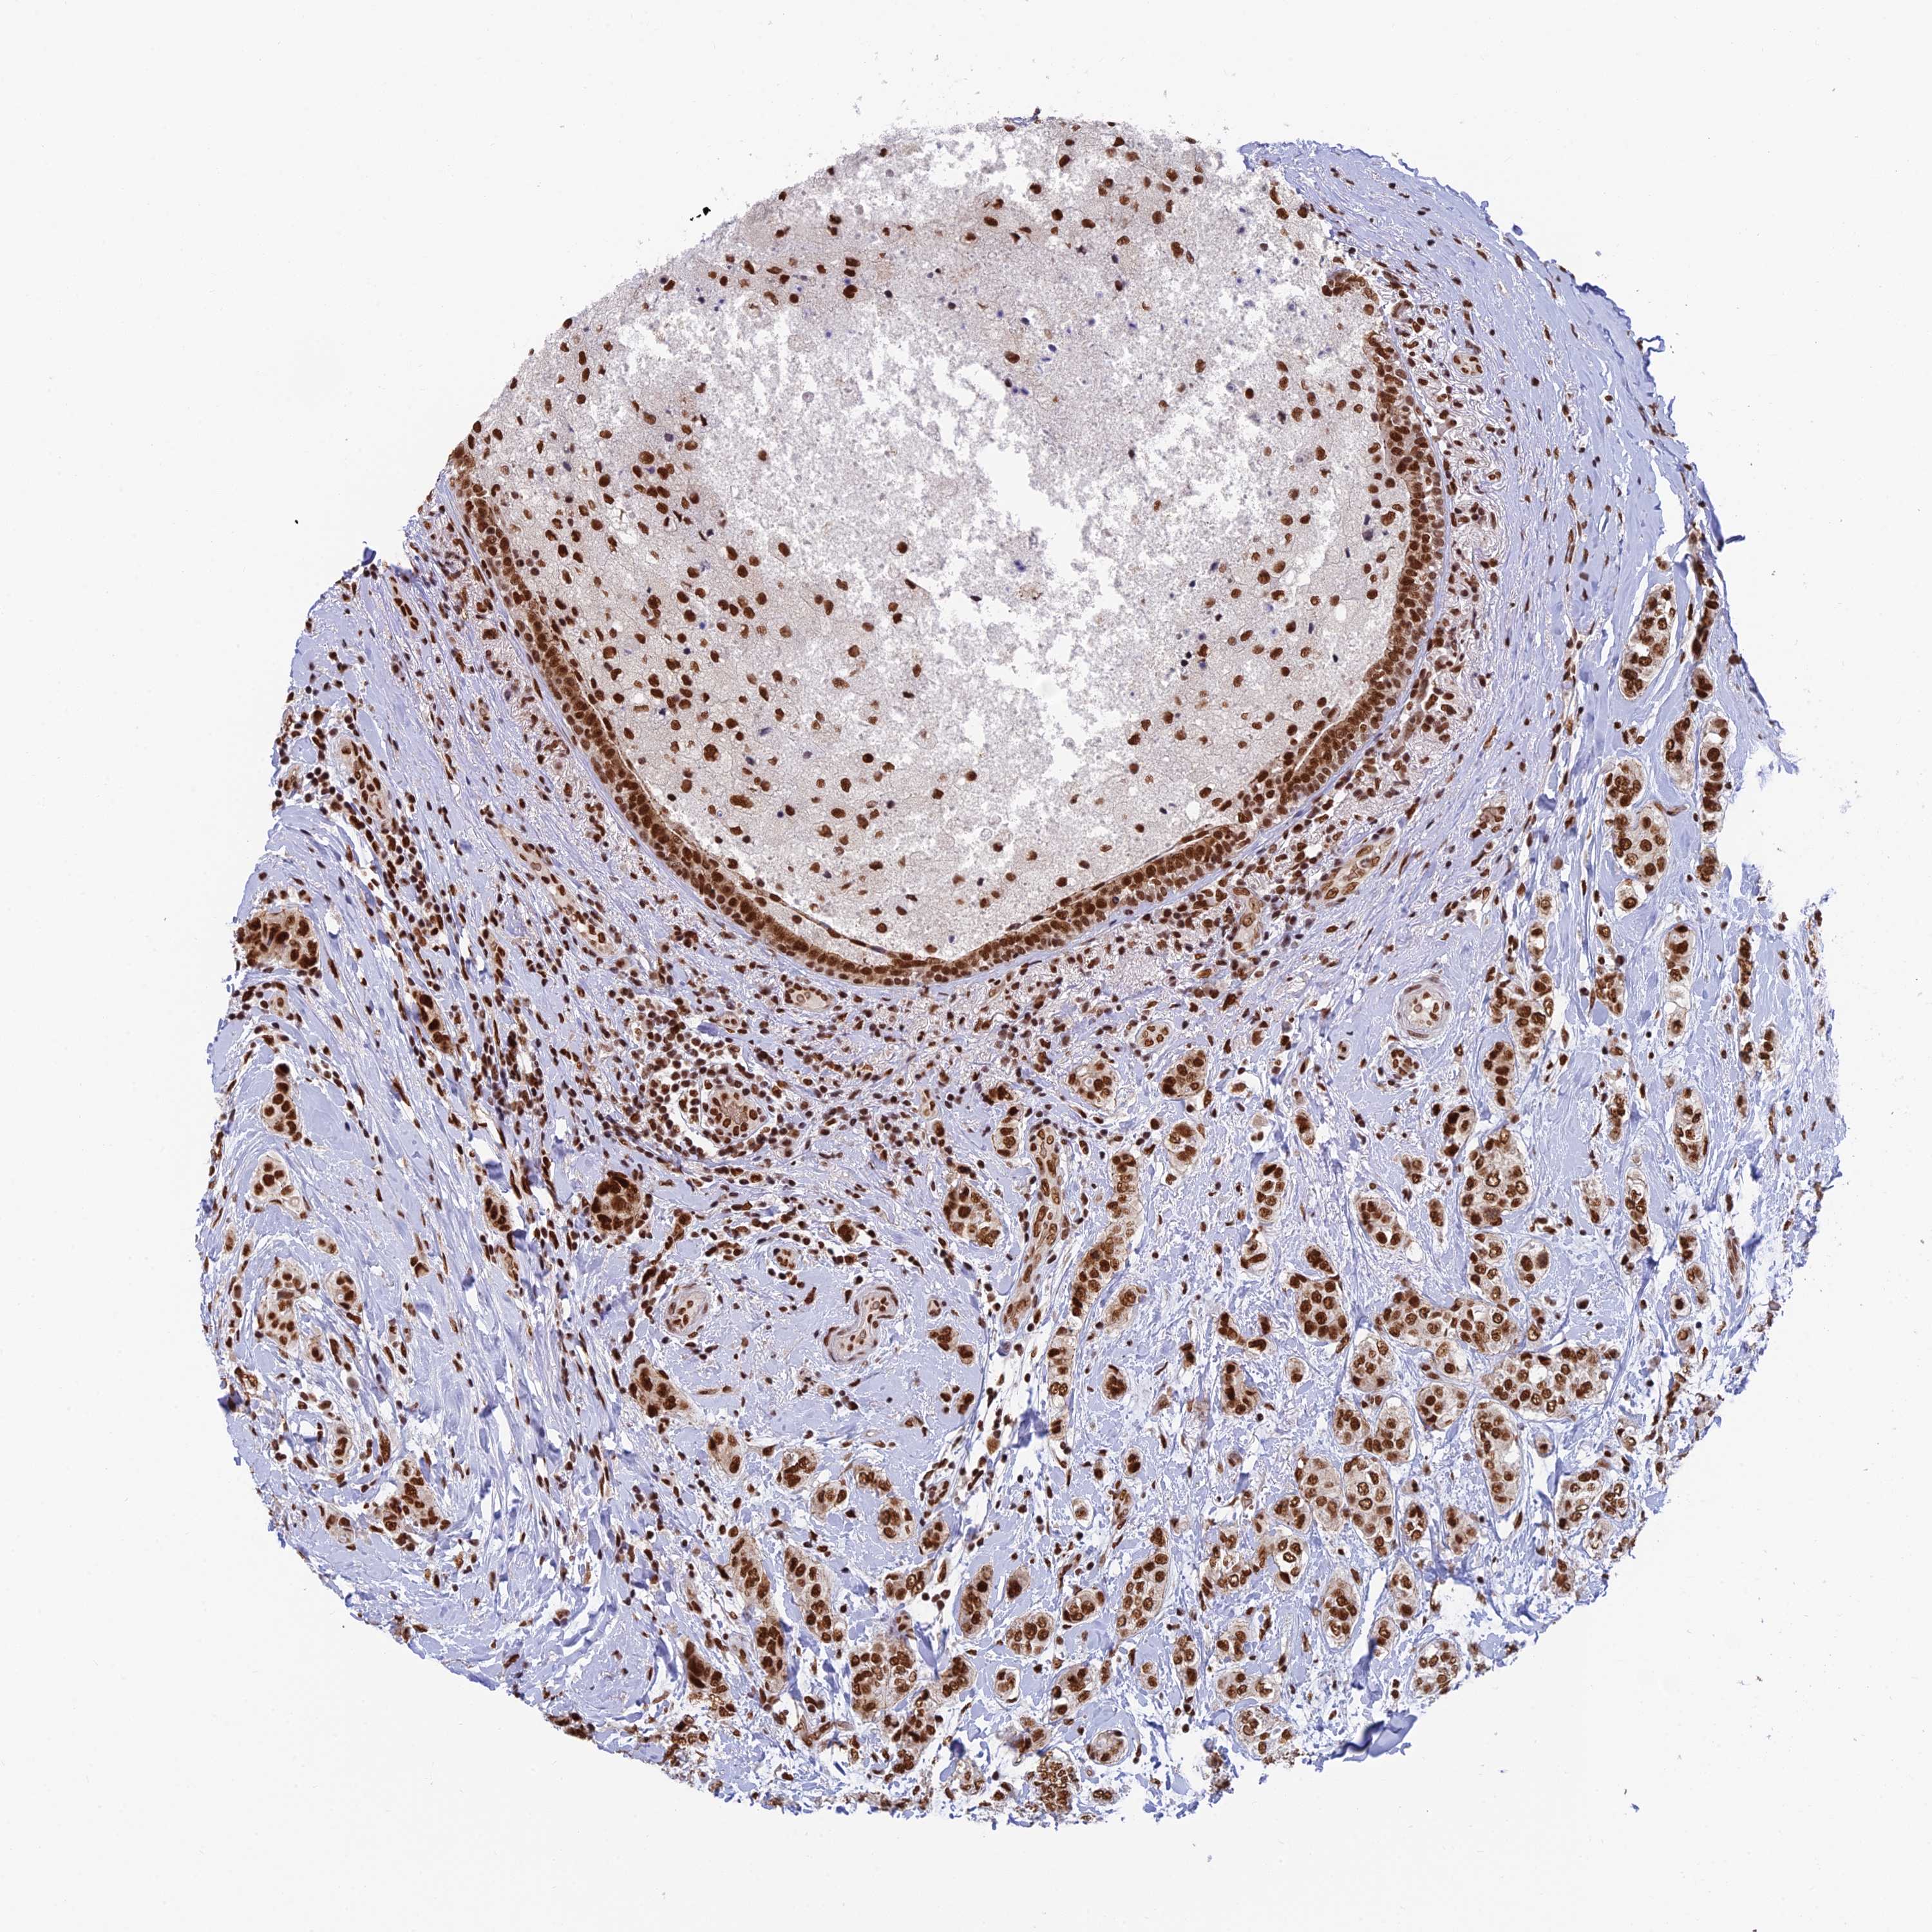

BRCA TCGA BRCA VALIDATION PROTEIN EXPRESSION